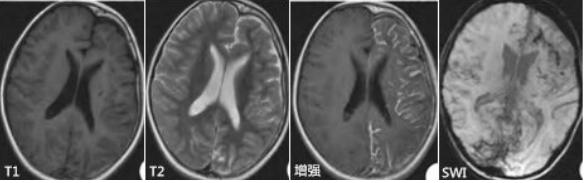

颅脑MRI表现:一侧大脑半球萎缩性改变(脑室扩大、外侧裂和脑沟增宽、脑回变小),伴有相应部位的灰质或白质萎缩和T2WI、FLAIR高信号,深部灰质核团(尾状核和壳核)也可受累,无颅骨代偿性改变。少数早期患者可表现为暂时性局部皮质肿胀及T2WI、FLAIR高信号。